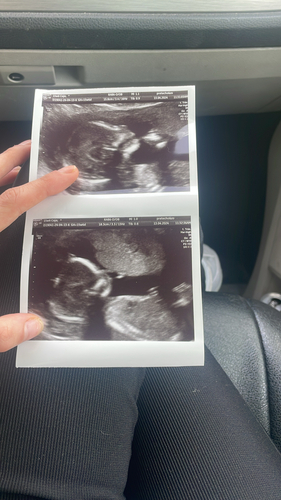

Wat ze hebben gezien op de echo:

- volledige AVSD hartafwijking

- verdikte nekplooi van 4,7mm

- vocht in hoofd tot en met de oksel

- 2 cystus in de hals

- vergrote nierbekken

- grote teen wijkt flink af van de andere tenen

En ik ben op dit moment 17 weken zwanger.. de kans is groot dat er alleen maar nog meer afwijkingen bij komen die ze nu nog niet kunnen zien..